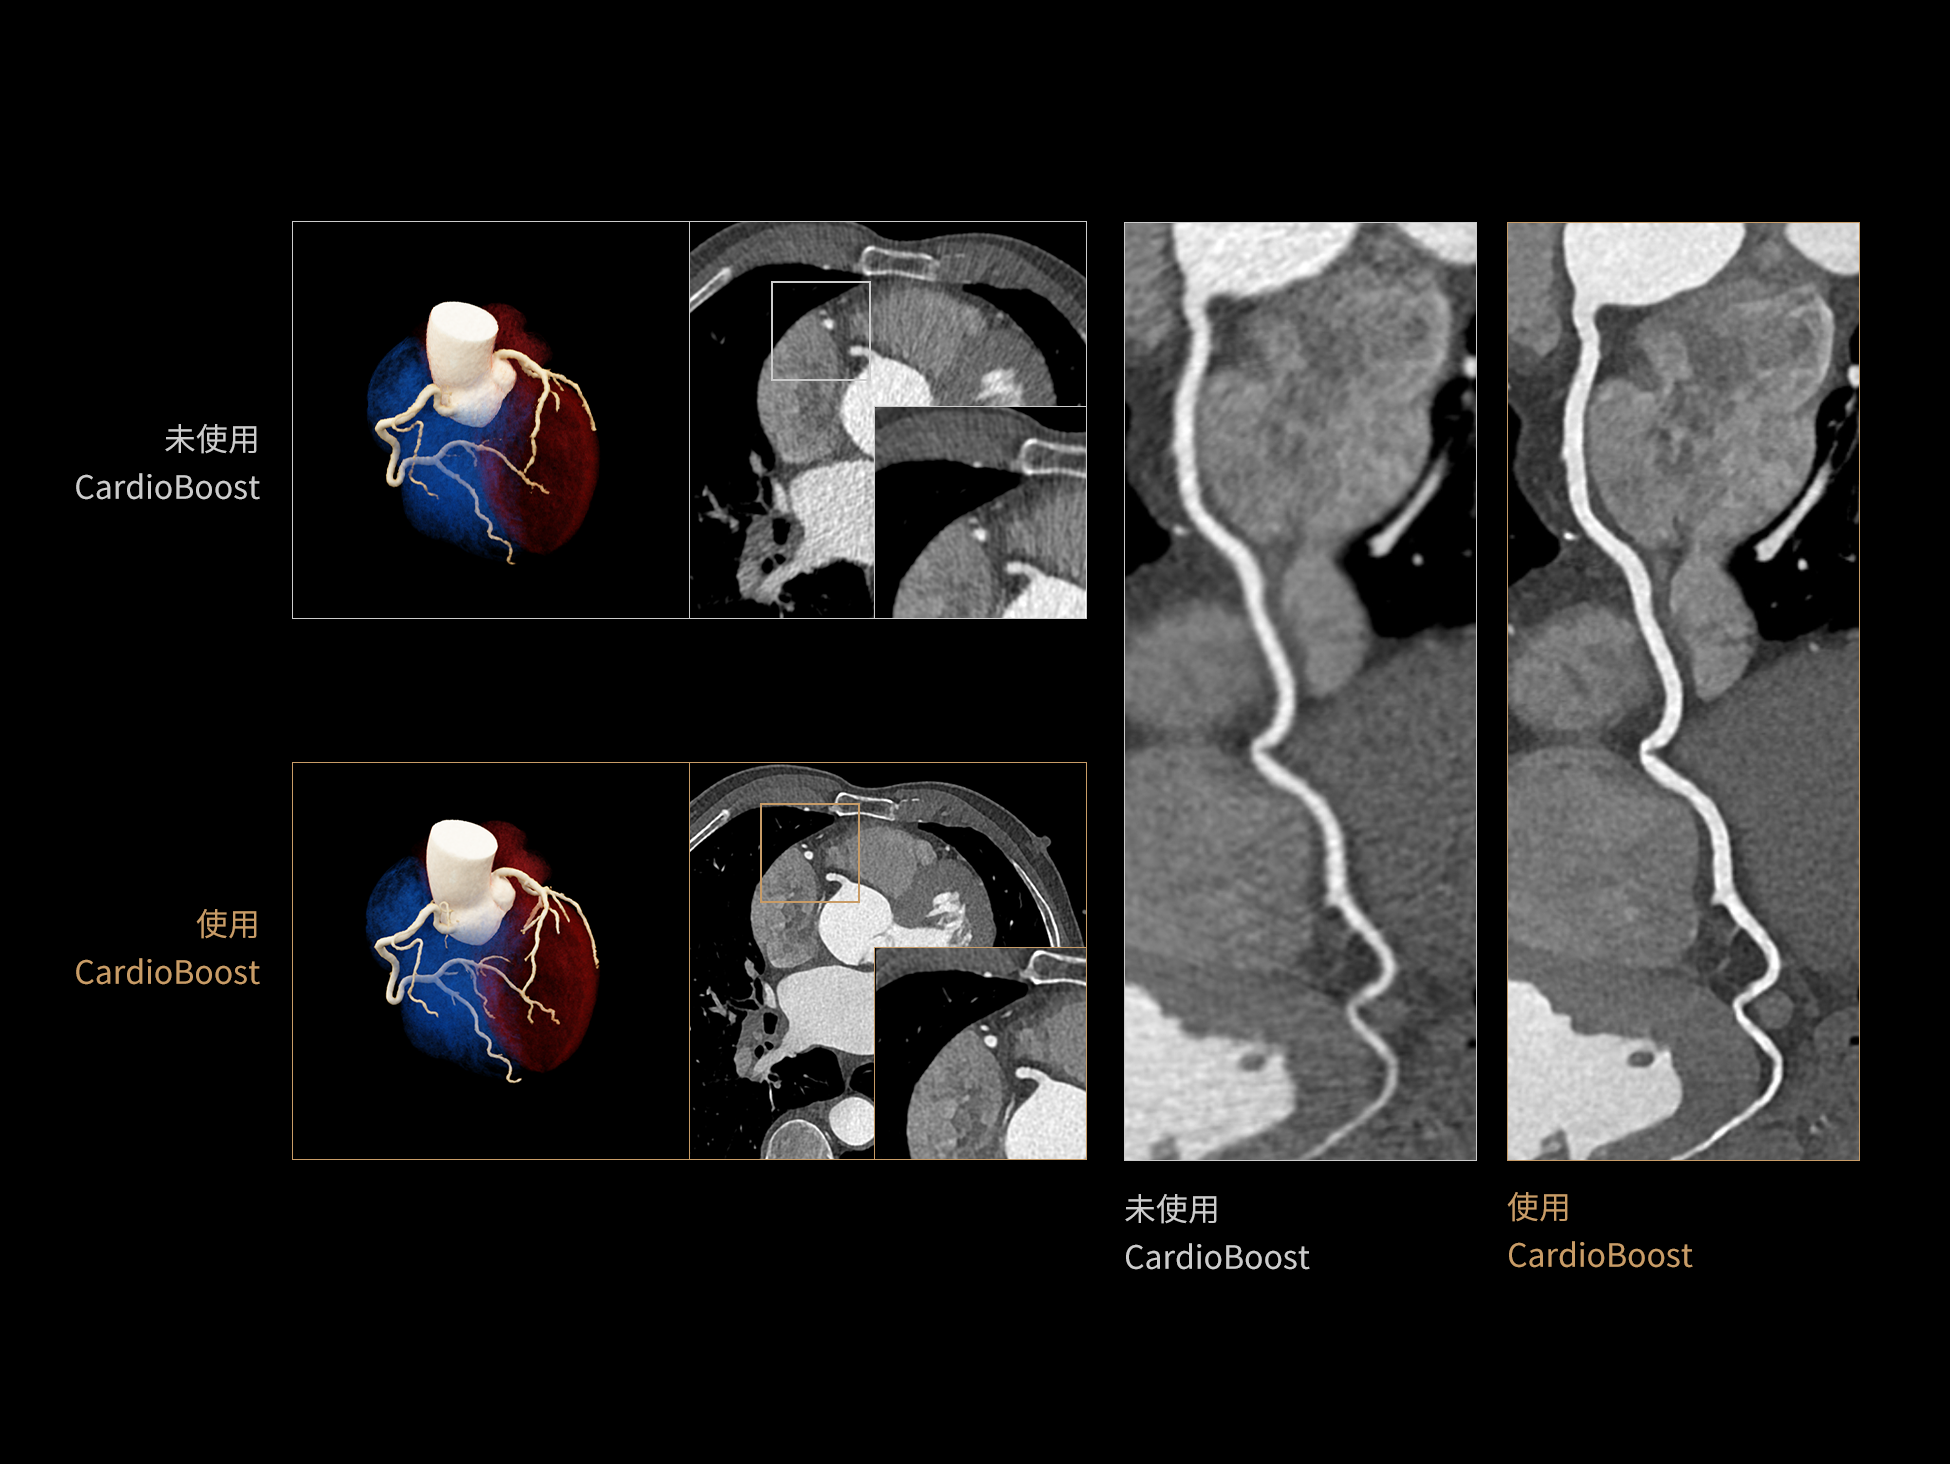

CardioCapture:AI冠脉运动追焦技术

CardioCapture 算法在冠脉运动伪影校正中采用全局化、系统化的处理策略。以目标时相为核心,重建多个相邻时相图像,利用深度学习技术提取连续时相中的冠脉树结构,构建时相间的运动模型,并对分段重建图像进行精准校正。通过这一过程,CardioCapture 可实现等效21 ms的超高时间分辨率,大幅提升冠脉图像清晰度与判读可靠性。

传统的血管提取通常基于CT值阈值和固定的冠状动脉模型,这种方法常常会失效,尤其是对于存在运动伪影的血管。 CardioCapture 算法基于深度学习网络,充分学习各类冠脉图像,以适应不同冠脉场景,精准高效完成冠脉及中心线提取,相较于仅基于CT 值和固定解剖模型的传统算法,CardioCapture 对于小血管及末端血管显示优势更加显著。

冠脉运动伪影校正过程

有效提取冠脉分支